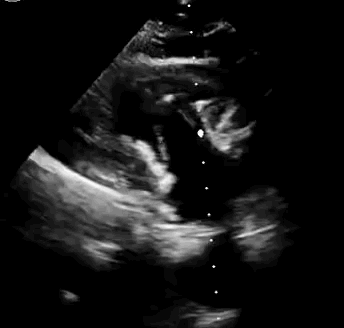

本次臨床前研究經(jīng)右側(cè)頸靜脈置入LuX-Valve Plus輸送系統(tǒng)可調(diào)彎鞘管,在DSA及超聲引導(dǎo)下將人工三尖瓣瓣膜植入到原有三尖瓣位置,利用獨(dú)特的錨定技術(shù)將人工瓣膜支架可靠固定在預(yù)定的位置。

上海中山醫(yī)院葛均波院士、錢菊英院長、周達(dá)新教授、潘文志教授、潘翠珍教授、李偉教授共同完成此次臨床前研究。術(shù)后葛均波院士對(duì)Lux-Valve Plus的器械操作性能給予了高度評(píng)價(jià),DSA和超聲影像也顯示出在本次研究中Lux-Valve Plus的安全性和有效性俱佳。